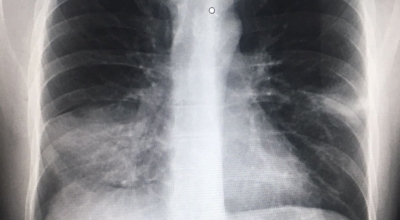

폐렴 증상이 있는 경우 X선 촬영 및 배양 검사로 진단할 수 있답니다. 필요에 따라 소변, 혈액, 혈청 검사, CT 등을 추가로 실시합니다. 폐렴 진단을 받은 환자는 일반적으로 입원을 권장하지 않지만 젊거나 기초질환이나 호흡곤란이 심한 경우, 고령, 임신 등의 경우 병원에 내원하여 상황에 맞는 신속한 치료와 상태 개선, 위험관리를 받는 게 좋아요.